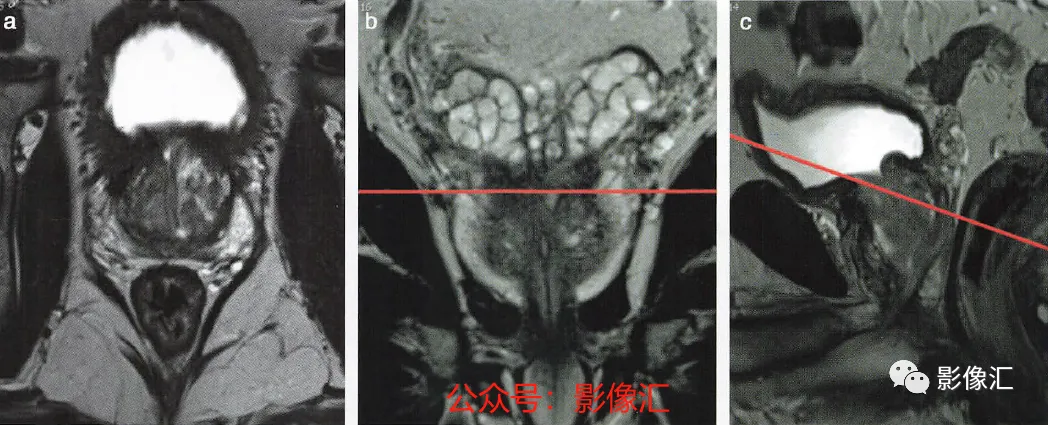

5. 前列腺底部水平的横轴面(图2.23)